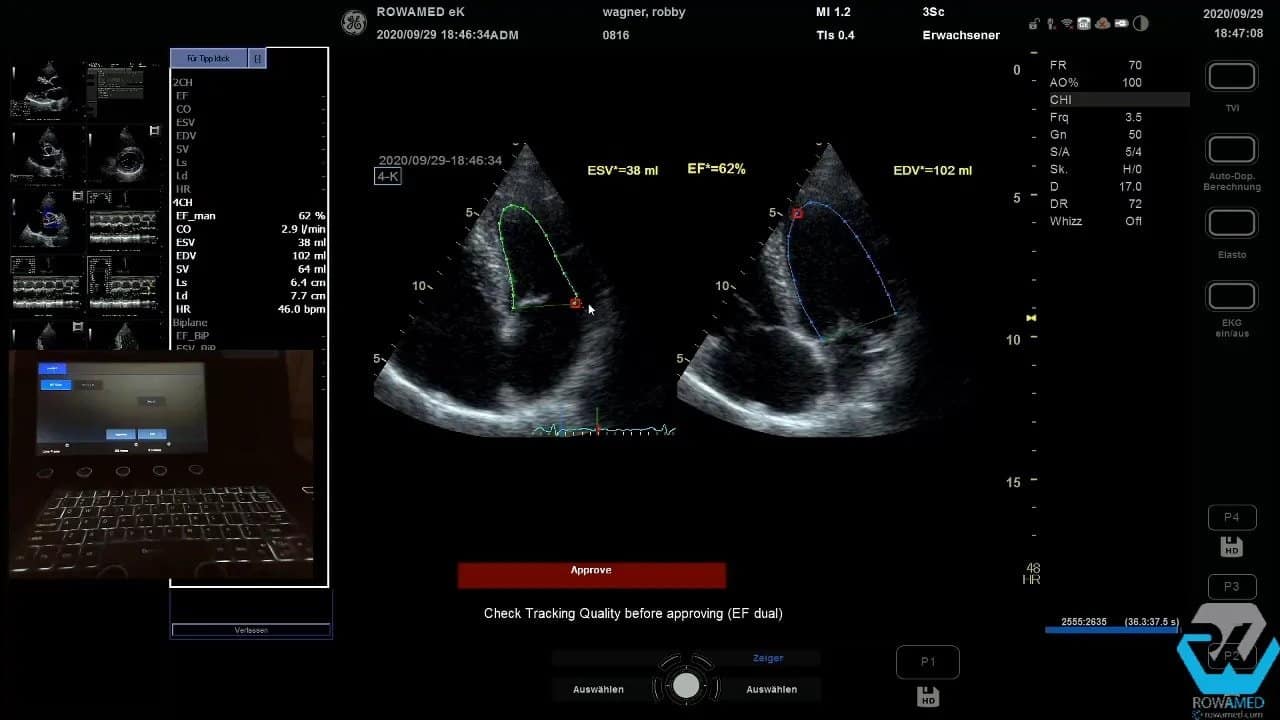

Step 8: Die Ejektionsfraktion manuell und automatisch bestimmen

Die linksventrikuläre Ejektionsfraktion gehört zu den Kernparametern der Transthorakale Echokardiographie. Im Vierkammerblick wird dazu zunächst das enddiastolische Volumen, danach das endsystolische Volumen bestimmt. Die Umfahrung des Endokards muss sauber erfolgen. Kleine Ungenauigkeiten an der Basis oder am Apex verändern das Ergebnis sofort.

Im Beispiel ergab die manuelle Volumenmethode eine EF von 60 Prozent bei leicht vergrößertem linken Ventrikel. Auch hier gilt wieder: Bitte immer an die Körpergröße und Körperoberfläche denken.

Danach kam die automatische EF-Bestimmung zum Einsatz. Solche Tools sind im Praxisalltag hilfreich, aber nur dann, wenn die Bildqualität stimmt und das EKG korrekt erkannt wird. Anfangs verweigerte das System die Berechnung wegen unzureichender EKG-Qualität. Nach erneutem Versuch funktionierte es. Im Vierkammerblick wurden zunächst 58 Prozent ermittelt, nach Korrektur der Tracking-Punkte sogar 69 Prozent.

Anschließend wurde die automatische Berechnung im Zweikammerblick wiederholt. Dort war die Endokarderkennung gut, die EF lag bei 63 Prozent. Zusammen ergab sich eine biplane EF von 66 Prozent.

Praxisregel: Verlassen Sie sich nie blind auf die Automatik. Die automatische Konturerkennung ist eine Hilfe, ersetzt aber nicht die fachliche Kontrolle. Genau darin zeigt sich die Qualität einer guten Transthorakale Echokardiographie.